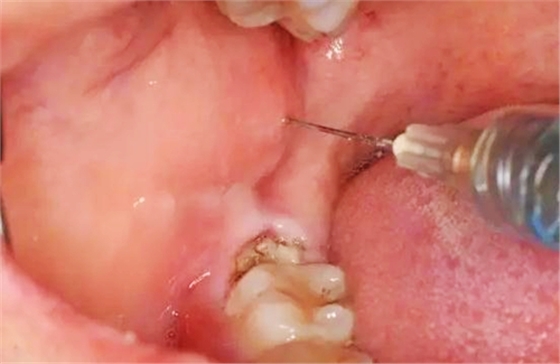

圖5.局部無(wú)痛阻滯麻醉